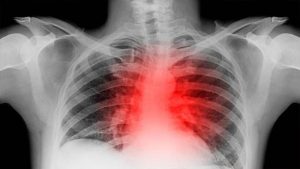

नई दिल्ली: हार्टबर्न की समस्या से रोजोना ना जाने कितने लोग परेशान रहते हैं. हार्टबर्न में इंसान को छाती के ठीक बीच में तेज जलन महसूस होती है. ये दिक्कत कुछ मिनटों से लेकर कई घंटों तक आपकी मुश्किलें बढ़ा सकती है. ये कई बार प्रेग्नेंसी, गेस्ट्रोइसोफेगल रिफ्लक्स डिसीज (GERD) या एंटी-इनफ्लेमेटरी ड्रग्स लेने की वजह से हो सकता है.

लेकिन छाती में होने वाली ये जलन कुछ मामलों में गंभीर बीमारी का संकेत भी हो सकते हैं. एक हालिया स्टडी में दावा किया गया है कि हार्टबर्न की समस्या कैंसर और हार्ट अटैक का जोखिम बढ़ने से भी जुड़ी हो सकती है. इसलिए शरीर में इसके वॉर्निंग साइन देखते ही आपको तुरंत डॉक्टर से संपर्क करना चाहिए.

हार्ट अटैक : हार्ट अटैक के मामले में भी कई बार लोग इसे हार्टबर्न समझकर नजरअंदाज कर देते हैं. इनमें फर्क समझने के लिए कुछ लक्षणों पर ध्यान देना जरूरी है. सीने में दर्द, तेज हार्टबीट, चिपचिपी त्वचा, इनडाइजेशन और जी मिचलाना जैसे लक्षण हार्ट अटैक का वॉर्निंग साइन हो सकते हैं. सीने में जलन के साथ दर्द, मुंह का कड़वा स्वाद, लेटने पर दर्द बढ़ना, चटपटा खाने के बाद गले तक जलन बढ़ना हार्टबर्न के प्रमुख लक्षण होते हैं.